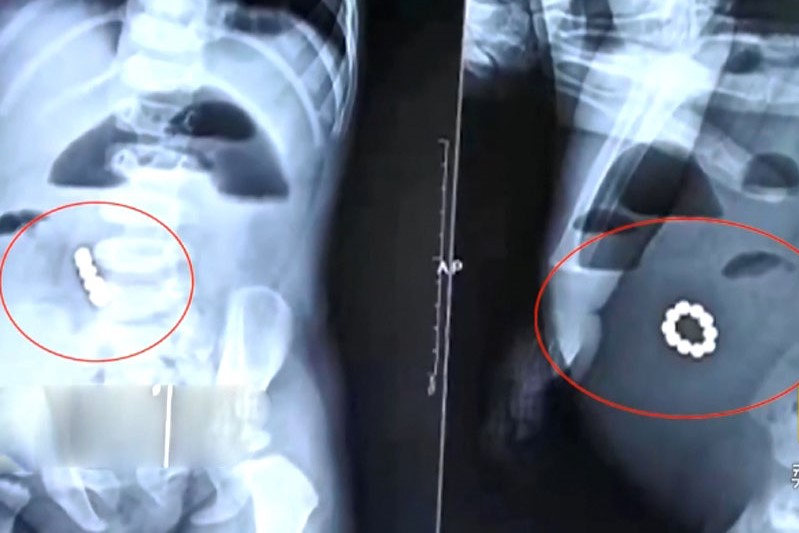

男嬰腹中的磁力珠已形成一串手環。圖:互聯網

【橙訊】家長稍不留神,幼兒或會誤吃東西,情況可大可小。最近山東淄博市婦幼保健院上周五(12日),接診了一名1歲8個月大的男嬰。男嬰當地患有腹痛,X光片顯示,男嬰的肚子裡可能有一串手鏈。

據X光片顯示,手鏈大概位於男嬰的胃或腸道內,繩子沒斷,各個珠子都串在一起,醫生一度表示男嬰危殆。

醫生其後決定立刻通過手術,為男嬰取出消化道內的手鏈。但在最後一次會診時,他們驚訝的發現,這手鏈突然散開了,珠子在男嬰的胃和腸道裡不斷變換位置。其後從男嬰家長口中得知,應該是幾個帶有磁性的鐵珠。

手術開始後,醫生們通過腸道穿孔的位置,迅速找到了4顆磁力珠;然後,他們順著男嬰的胃和腸子一寸、一寸地探查,又找到了6顆磁力珠。當這10顆磁力珠被放置在一起時,它們迅速圍攏起來,形成了手鏈的模樣。